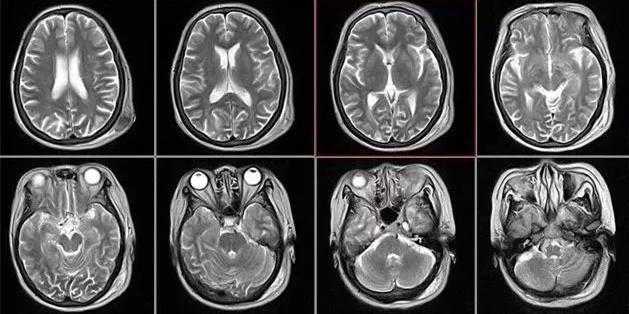

核磁共振摇一摇再看

核磁共振仪使用较强大的磁场,使人体中所有水分子磁场的磁力线方向一致,这时磁共振机的磁场突然消失,身体中水分子的磁力线方向,突然恢复到原来随意排列的状态。简单说,就相当于用手摇一摇,让水分子振动起来,再平静下来,感受一下里面的振动。所以,核磁共振也被戏说为是摇摇看的检查。